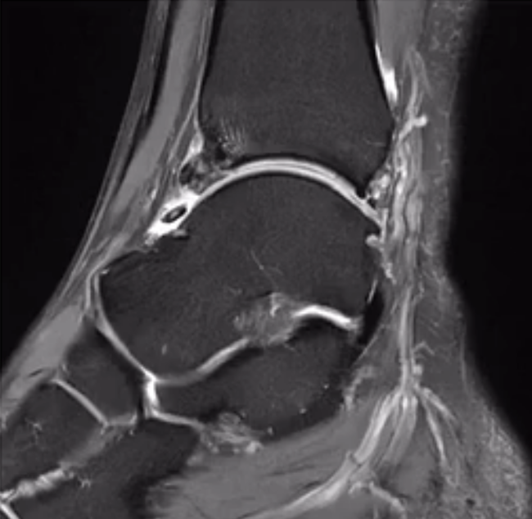

图5:核磁共振可清楚地显示胫骨增生骨赘伴骨髓水肿,关节前缘游离体,前隐窝滑膜炎。

▶增生骨赘伴骨髓水肿;

▶距骨穹隆软骨损伤;

▶骨赘骨折或关节前缘游离体

▶前隐窝滑膜炎。